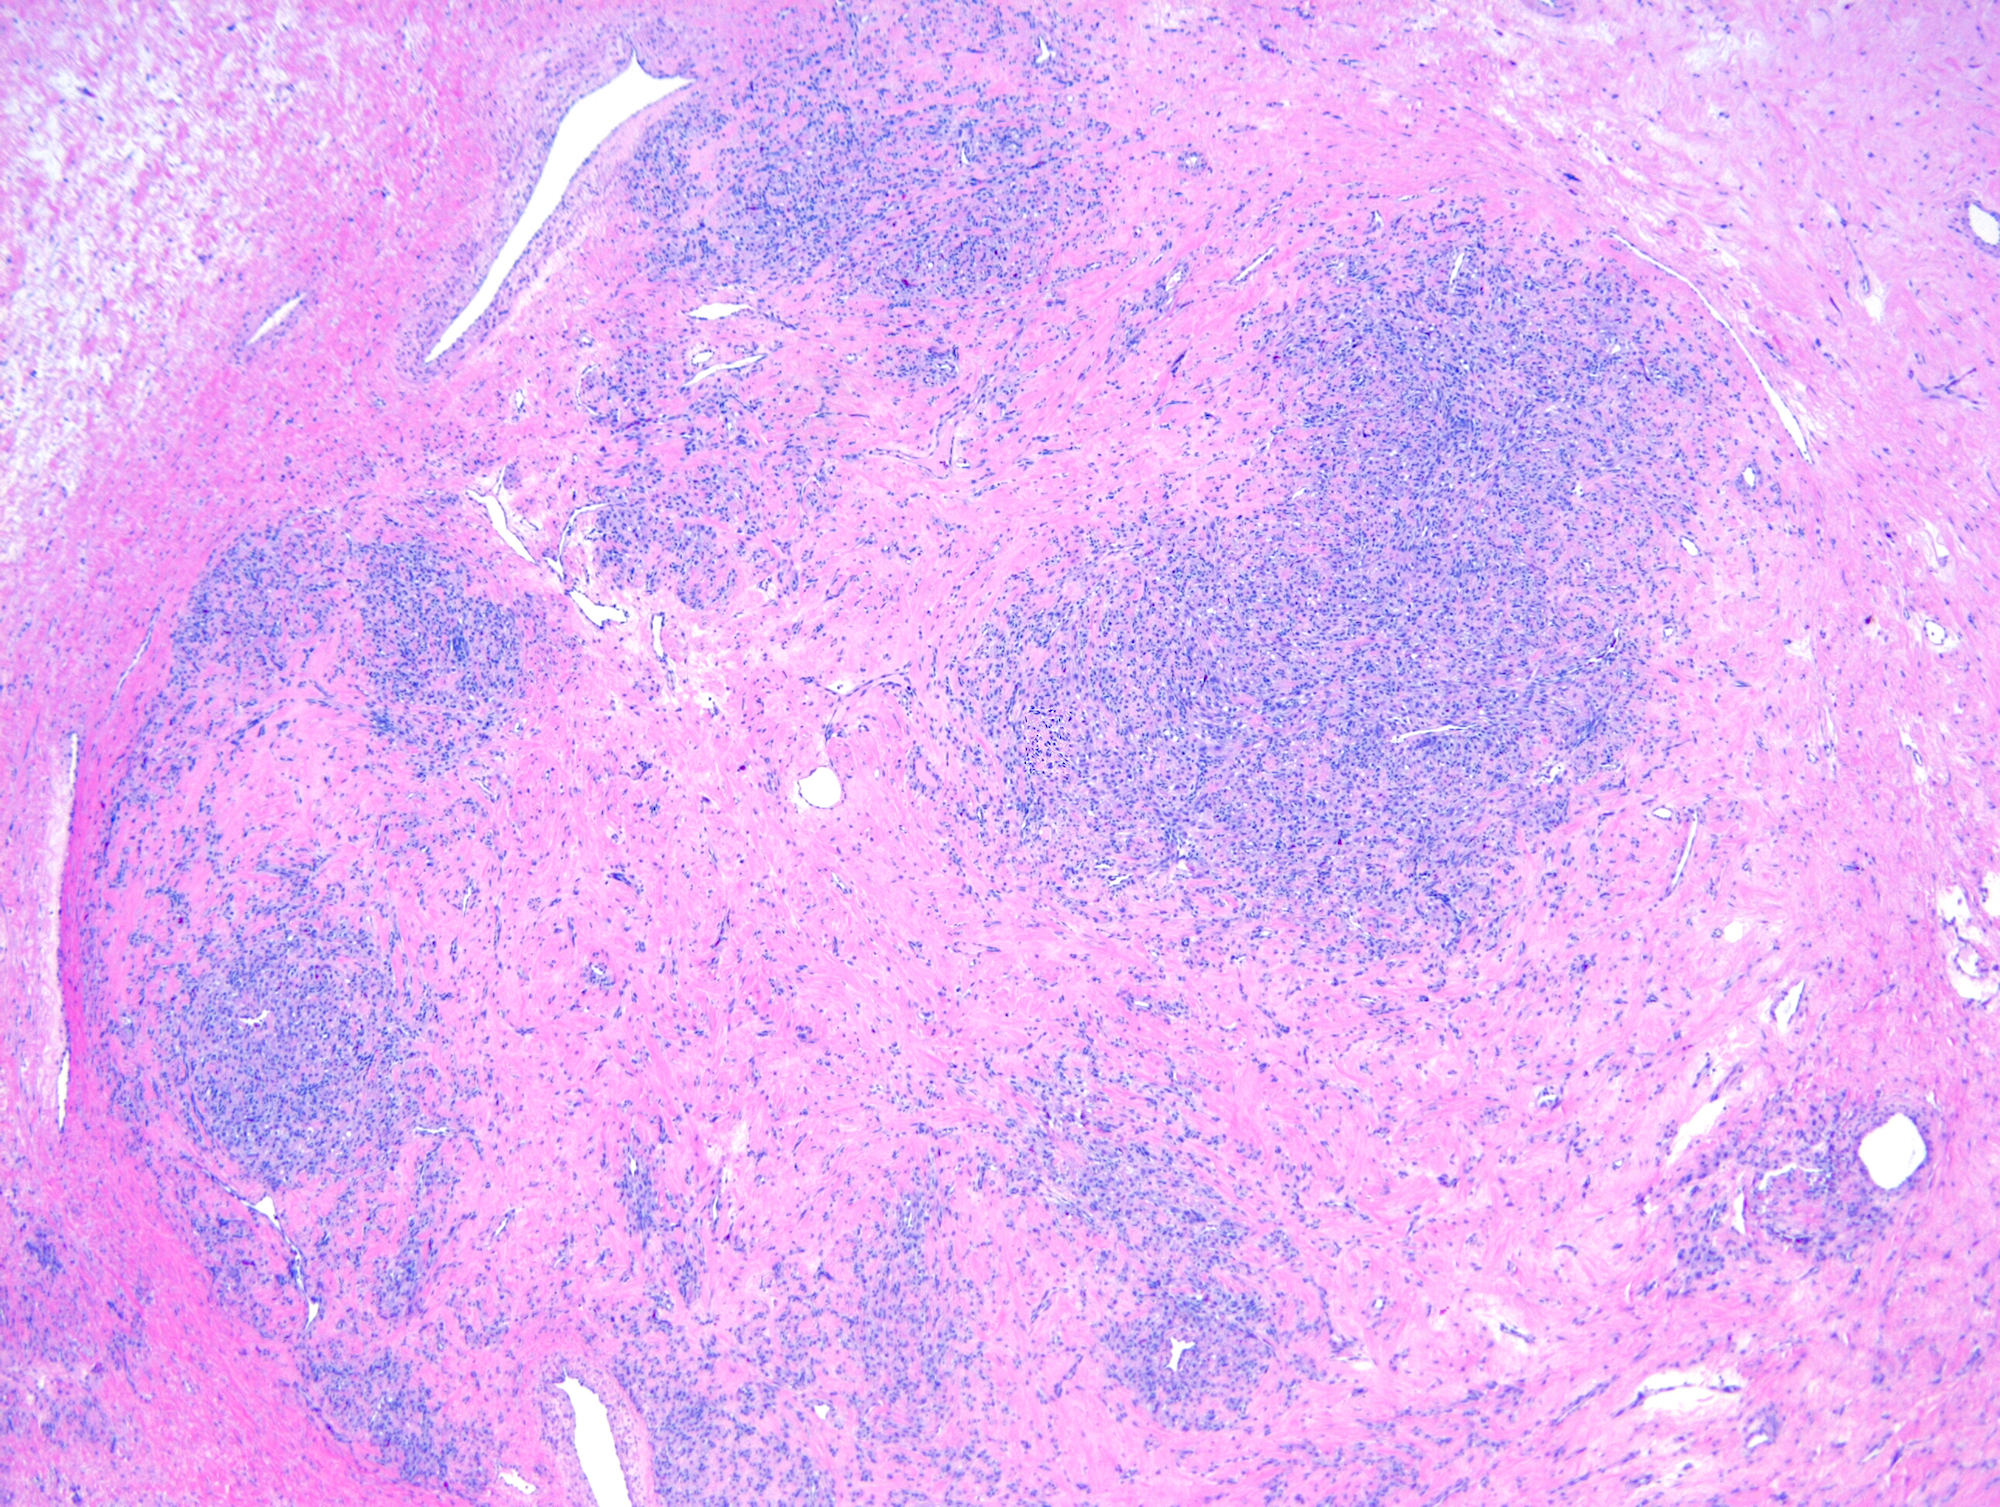

Microscopic (histologic) description

- Alternating cellular and hypocellular areas impart a pseudolobular appearance

- Hypocellular foci may be ill defined in pregnancy due to expansion of the pseudolobules by lutein cells (Int J Gynecol Pathol 2015;34:357)

- Thin, dilated and branching hemangiopericytoma-like vasculature is often conspicuous in both components

- Pseudolobules comprised of a jumbled admixture of epithelioid (lutein) and spindled cells with minimal atypia

- Hypocellular areas can be edematous, collagenous (variably keloid-like) or myxoid

- References: Cancer 1973;31:664, Histopathology 2022;80:360

Microscopic (histologic) images